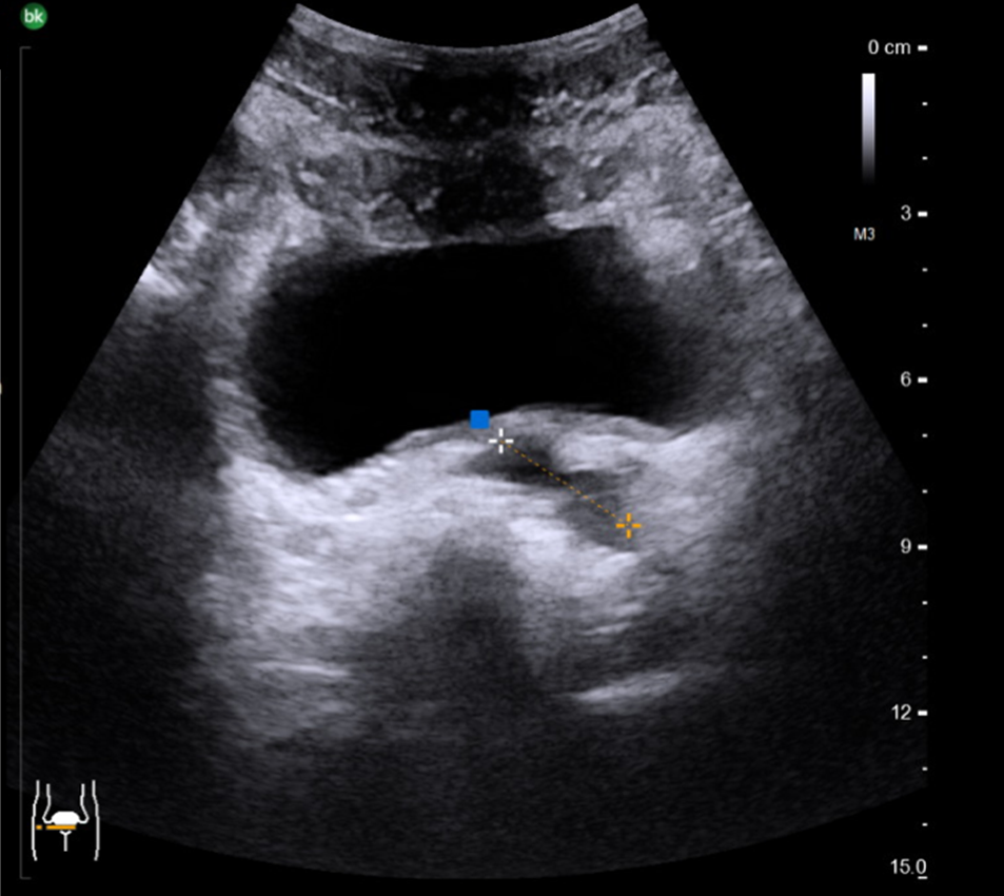

Sonographisch ließ sich eine prominente linke Samenblase im transvesikalen Ultraschall darstellen, sodass eine Bildgebung des Beckens mittels MRT durchgeführt wurde (Abb. 1 und 2). Hier zeigte sich ein zystisch dilatiertes Vas deferens sowie eine deutlich dilatierte Samenblase links bei nicht darstellbarem Vas deferens und Samenblasenagenesie rechts. Zum Ausschluss eines Zinner-Syndroms erfolgte neben einer Sonographie des oberen Harntrakts auch die weitere Diagnostik mittels MRT Abdomen. Bei regelrechtem Befund beider Nieren konnte ein Zinner-Syndrom ausgeschlossen werden.

Abb. 2

MRT Becken im Transversal- (a) und Sagittalschnitt (b) mit Anschnitt der zystisch erweiterten linken Samenblase